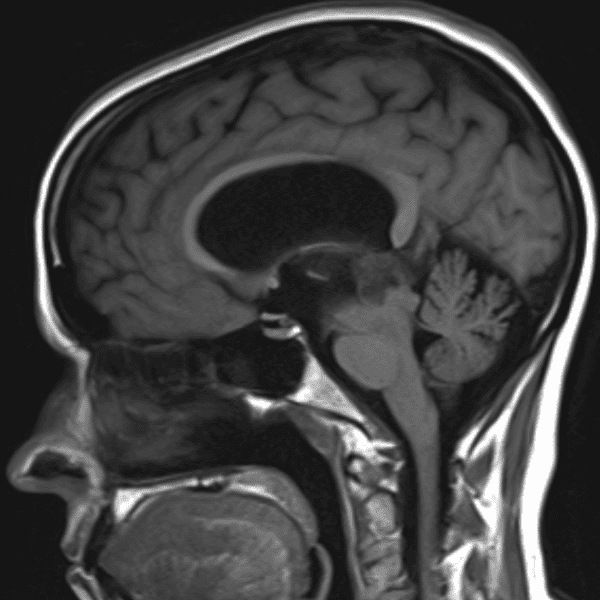

Classic Cases